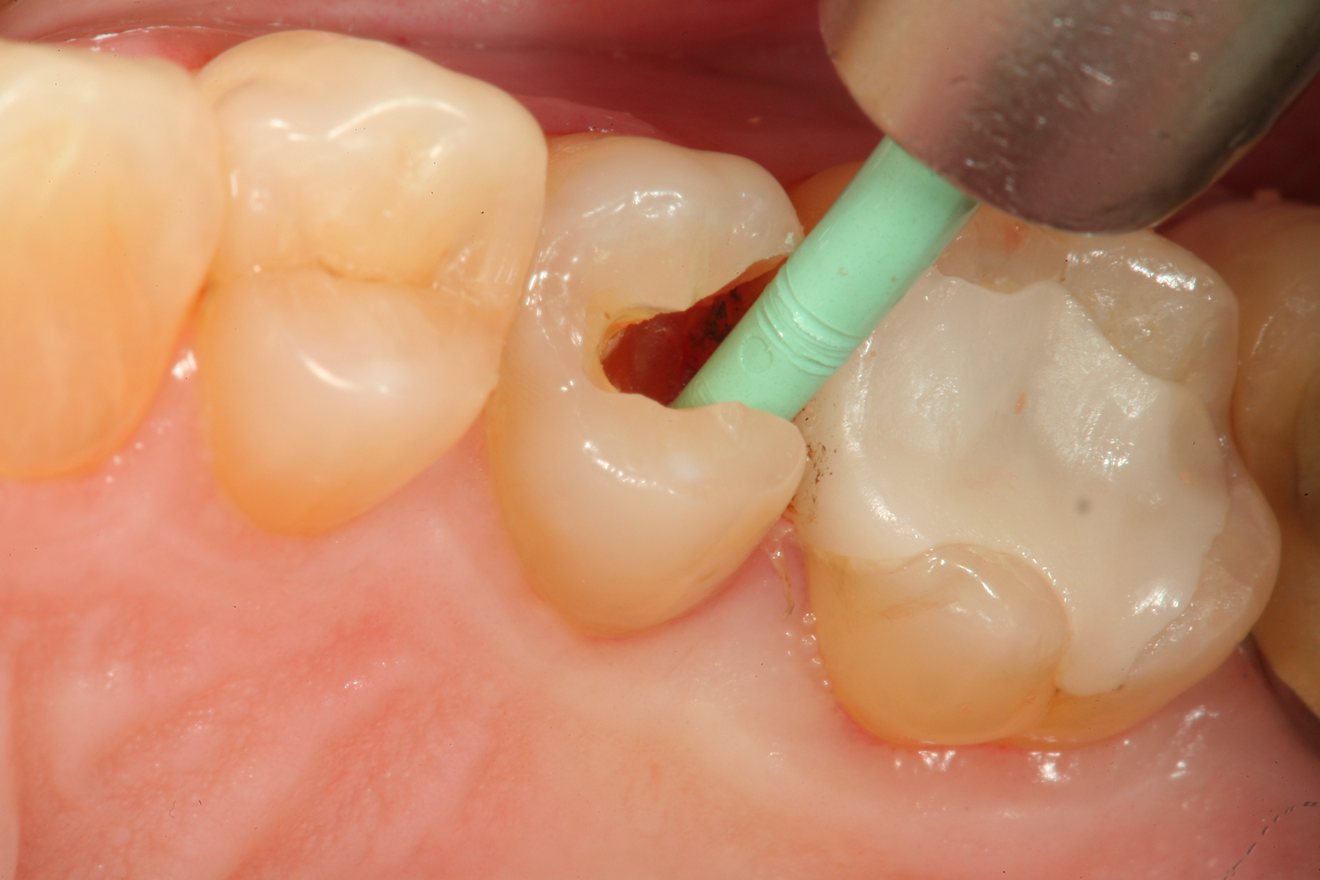

Fig 3	After a fissurotomy bur is used to conservatively open into the groove, a rather extensive carious area is discovered.

Figure 3

Fig 4.	The lesion is excavated with a Smart BurII (SS White) to remove infected dentin only.

Figure 4

A 66 year-old female patientpresented with a "stained" occlusal groove in tooth No. 13 that did not "stick" with an explorer tip (Figure 1).  Upon radiographic examination (Figure 2), a rather large carious lesion was discovered that encroached upon the dental pulp.  There were no other clinical or subjective signs to alert the clinician or patient to the extent of the damage that had already occurred in the tooth. Figure 3 through Figure 5 show selective caries removal using a round end plastic polymer bur (SmartBurII, SS White).  Before caries removal, isolation of the operative quadrant was achieved using Isovac (Zyris). Because of its Knoop hardness of 90, SmartBurII allows for removal of infected dentin only, while allowing affected dentin to remain for potential remineralization with a bioactive liner or base material.